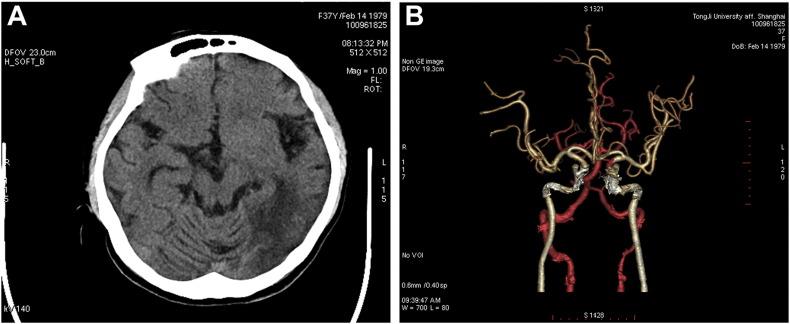

Mitochondrial myopathy, encephalopathy, lactic acidosis and stroke-like episodes (MELAS) is a clinical syndrome associated with mitochondrial disorders (MIDs). This report illustrates a case of MELAS syndrome with hypothyroidism and psychiatric disorders, which is different from the common clinical manifestations of MELAS syndrome, such as exercise intolerance, migraine-like headaches, hearing loss and seizures etc. There are considerable interests in the possibility that mitochondrial dysfunction may play a role in the pathogenesis of endocrine dysfunctions and psychiatric disorders in MELAS syndrome.

线粒体肌病、脑病、乳酸酸中毒和卒中样发作(MELAS)是一种与线粒体疾病(MIDs)相关的临床综合征。本报告阐述了一例伴有甲状腺功能减退和精神障碍的MELAS综合征病例,该病例不同于MELAS综合征的常见临床表现,如运动不耐受、偏头痛样头痛、听力丧失和癫痫发作等。线粒体功能障碍可能在MELAS综合征的内分泌功能障碍和精神障碍发病机制中起作用,这一可能性引发了人们相当大的兴趣。